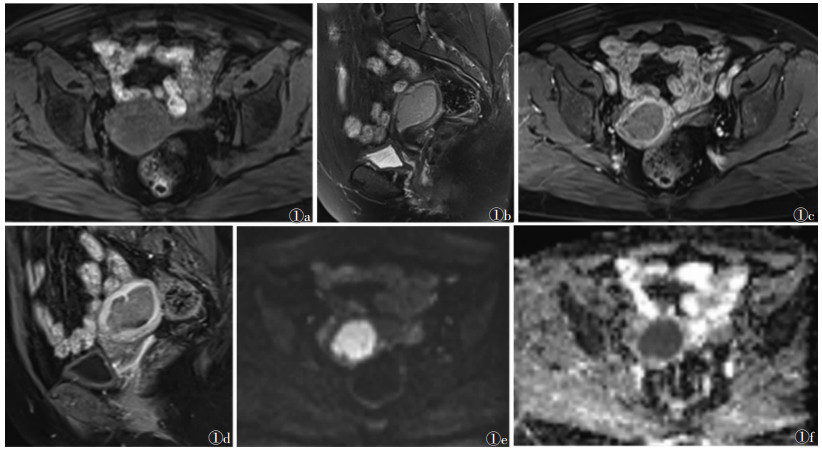

肿瘤平扫信号强度与子宫肌层信号相比,T1WI呈等或略低信号(图 1a),其中等信号40例,略低信号16例;T2WI呈略高信号51例(图 1b),高信号5例。56例增强扫描T1WI上子宫内膜癌组织均呈轻度渐进性强化,信号强度始终低于明显强化的外肌层(图 1c1d),肿瘤与子宫外肌层信号对比差在增强扫描后180 s达最大,与正常肌层对比非常明显。56例DWI均呈高信号(图 1e),ADC呈低信号(图 1f),ADC值平均为(0.904±0.185)×10-3 mm/s。

图 1 女,56岁,MRI示子宫腔内一大小3.6 cm×3.8 cm×4.4 cm肿块,手术病理证实为子宫内膜腺癌  1a  T1WI抑脂轴位,肿瘤呈稍低信号,边缘不清  1b  T2WI抑脂矢状位,肿瘤呈稍高信号  1c  T1WI抑脂增强轴位,正常子宫肌层明显强化,肿瘤轻度强化呈相对低信号  1d  T1WI抑脂增强扫描矢状位,肿瘤轻度强化呈相对低信号 1e DWI示肿瘤呈高信号  1f  ADC图肿瘤呈低信号,ADC值为0.889× 10-3 mm2/s